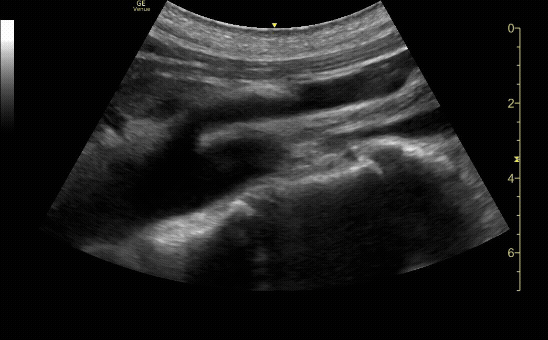

Proximal sagittal (long) view showing a dissection flap.

c/o Sohaib Amjad, MD